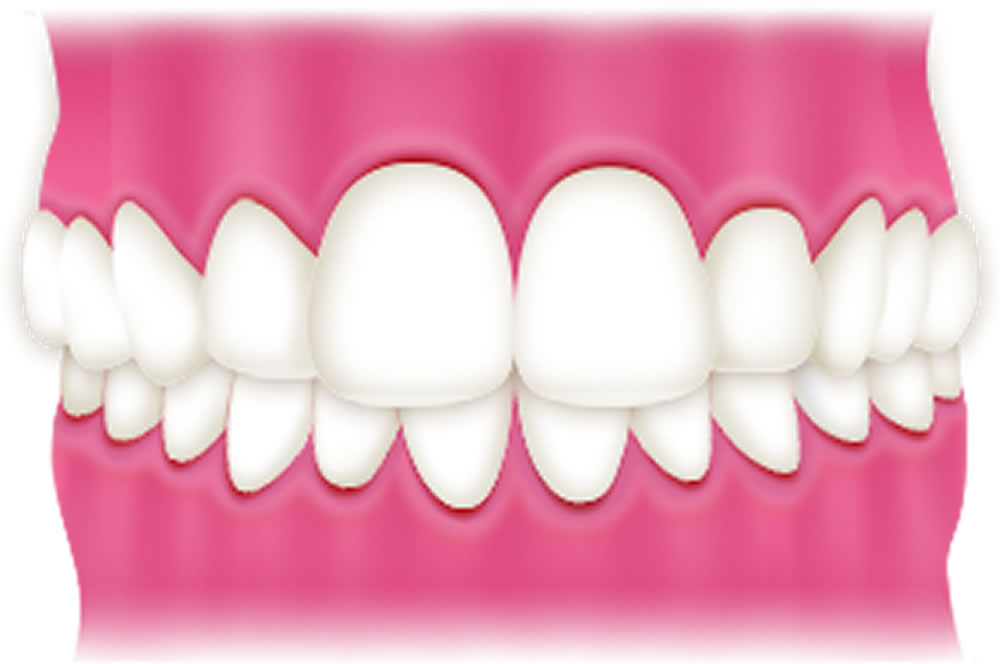

下顎前突(受け口)

下顎や下の前歯が前方に突出した状態(受け口)です。見た目のコンプレックスにつながるほか、咀嚼時に顎へ負担がかかり、顎関節症のリスクが高まります。